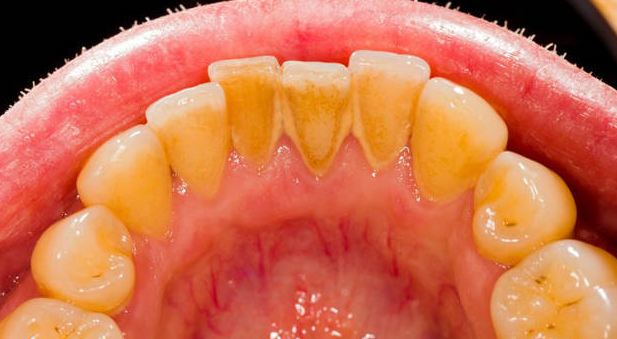

牙結(jié)石清除全攻略

牙結(jié)石,也稱為牙石,是牙齒表面形成的硬質(zhì)沉積物,主要由食物殘?jiān)?、?xì)菌及其代謝產(chǎn)物組成。如果不及時(shí)處理,牙結(jié)石不僅會導(dǎo)致口臭、牙齦炎等問題,還可能引起更嚴(yán)重的口腔疾病如牙周病。因此,珠海六和口腔醫(yī)院認(rèn)為了解如何有效預(yù)防和清除牙結(jié)石至關(guān)重要。

二、牙結(jié)石的危害

引起牙齦炎癥、出血

導(dǎo)致口臭

加速牙齒腐蝕

最終可能導(dǎo)致牙齒松動甚至脫落

四、牙結(jié)石的治療方法

超聲波潔牙術(shù):通過高頻振動去除牙齒表面的牙結(jié)石,是一種常見且有效的治療方法。

手動刮治:對于難以用超聲波設(shè)備清理的地方,牙醫(yī)會使用手動工具進(jìn)行細(xì)致的清潔。

激光治療:適用于較為嚴(yán)重的牙周病患者,能有效消除牙周袋內(nèi)的細(xì)菌和病變組織。